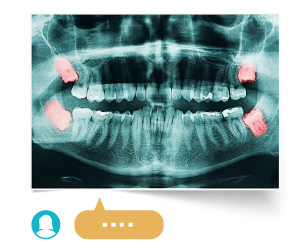

У вас есть снимок зуба?

Вы хотите получить мнение наших врачей по вашему случаю без визита в клинику?Стоматология на Бабушкинской

Пациент располагается на стоматологическом кресле в лежачем положении. Стоматолог устанавливает микроскоп так, чтобы он находился примерно в 25 сантиметрах над лицом пациента. Это комфортное расстояние, при котором вы не ощущаете никакого психологического давления. Врач располагается позади головы пациента, и дальнейшее лечение зубов происходит под микроскопом. Он оборудован видеокамерой, и все происходящее в поле зрения врача передается на монитор в кабинете. Вы можете увидеть состояние зуба до и после лечения.

Лечение каналов зубов под микроскопом

При воспалении пульпы инфекция проникает в корневые каналы. Так развивается пульпит — болезнь, при которой проводится лечение каналов с устранением инфицированных тканей, антисептической очисткой и тщательной герметизацией. Провести эти работы качественно, особенно если у зуба несколько корней, можно только под микроскопом.

На первом этапе лечения каналов стоматолог вскрывает пульпу, закладывает девитализирующую пасту и ставит временную пломбу. На втором этапе через несколько дней пломбу снимают, устраняют инфицированные ткани, очищают корневые каналы и герметизируют их гуттаперчей.